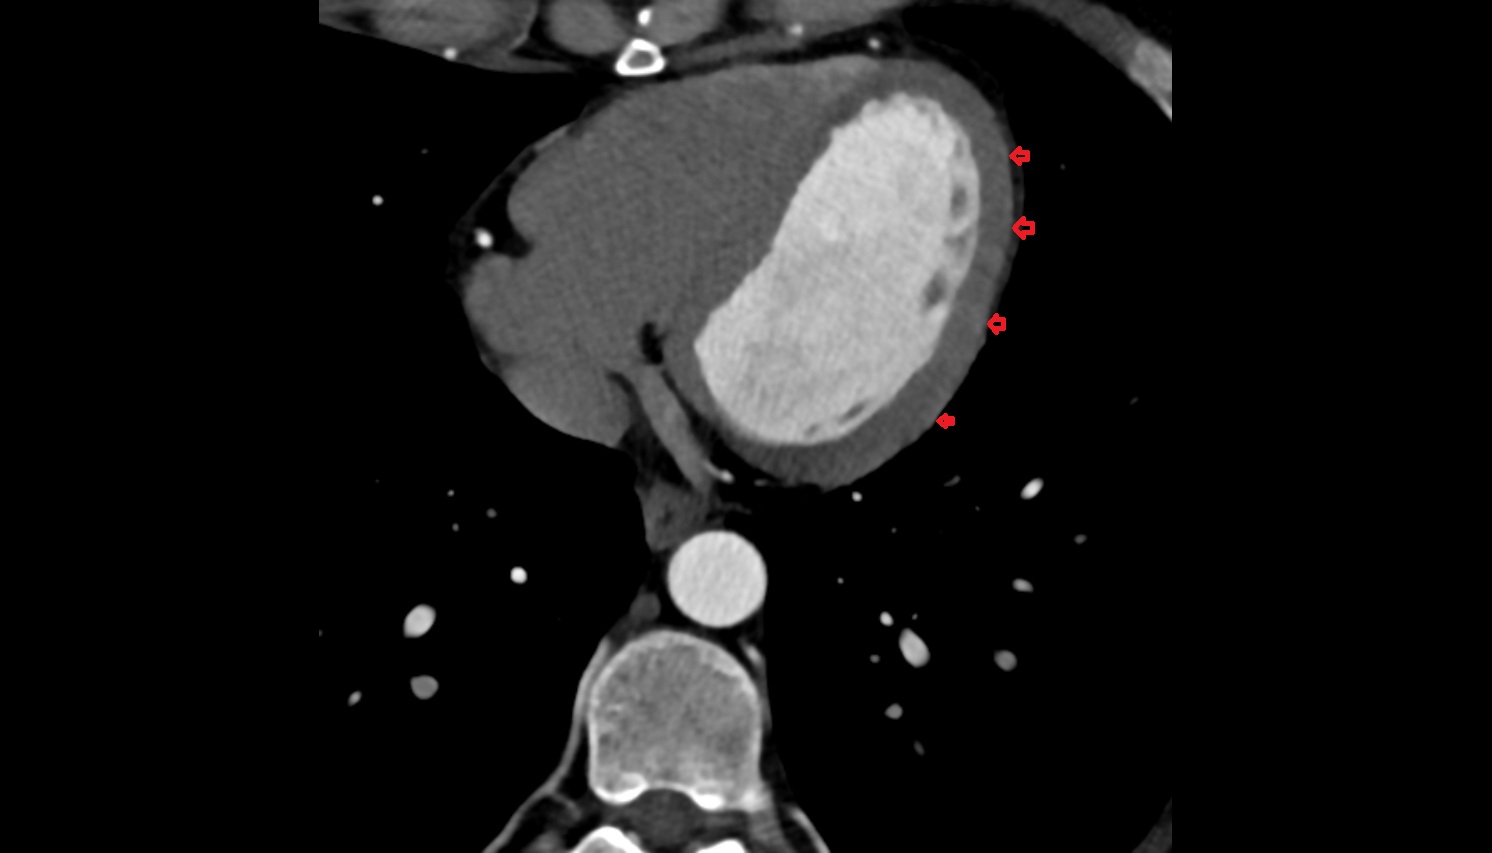

- Pericardium

- Heart

- Myocardium

- Epicardium

- Pericardial cavity